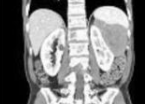

苏州治疗肾结节专业的医生科普:肾结节又叫肾脏肿瘤,是指肾脏局部组织变硬、钙化。一般肾脏结节分良性和恶性,90%的肾结节都是良性的。那么肾结节的出现会引发其他肾脏疾病的发生吗? 良性的肾结节 比如一些小的肾囊肿、错构瘤等,在结节比较小的时候又生长比较缓慢,而且对肾脏功能和结构的... [详情]

苏州看肾脏结节好的医生提醒:肾脏结节的另一种形式—肾囊肿,目前是肾脏比较常见的一种肾脏疾病,生活中有很多人以为肾囊肿只要吃点药就可以了,其实这种想法是严重错误的。肾囊肿的病患群还是比较广泛的,如果肾囊肿这种疾病得不到及时的治疗,会出现很多的危害。 感染,如果囊肿突然破裂,那么出... [详情]

苏州看肾结节好的医生提醒:苏州国医堂名医便民工作室主任叶盛德提道说,肾结节是一种由于肾脏组织变硬或钙化引起的特殊肉芽肿性疾病,肾结节是否严重取决于结节的性质,如果个人体质较好、是良性结节、病情较轻,一般不严重。现在查出肾结节的概率也是越来越高了,那么患肾结节居高不下的因素有哪几个... [详情]